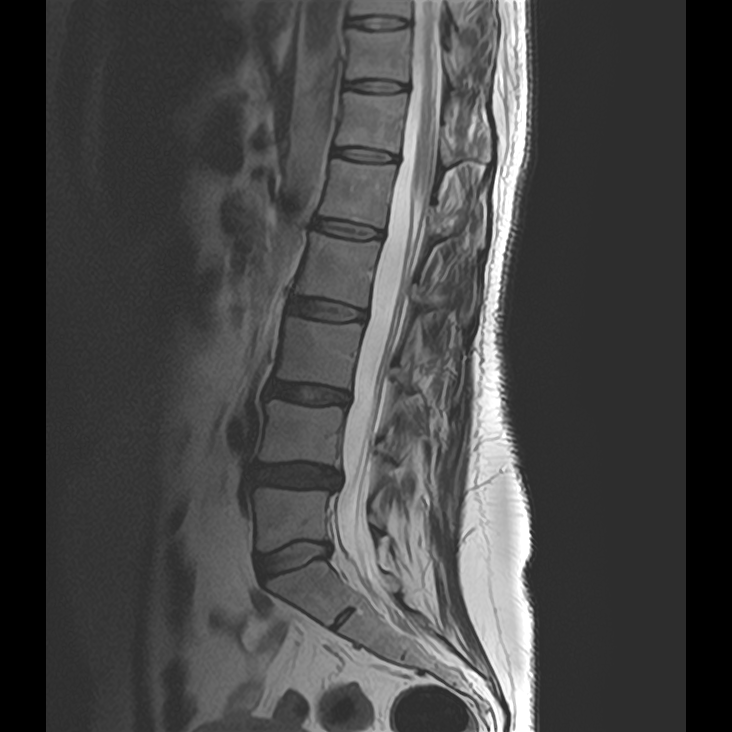

„Radikulární, tedy kořenové syndromy, patří mezi časté příčiny bolestí zad s vyzařováním do dolních končetin. Jsou způsobeny útlakem nervového kořene, nejčastěji výhřezem meziobratlové ploténky nebo zúžením páteřního kanálu,“ vysvětluje primářka neurologického oddělení Nemocnice Vyškov MUDr. Hana Kadlčíková.

Výkon je prováděn pod CT kontrolou, což zajišťuje přesné umístění léčebné směsi složené z kortikoidu, lokálního anestetika a kontrastní látky. Podle primáře radiodiagnostického oddělení MUDr. Pavla Kedera jde o efektivní a šetrný výkon, který lze provést ambulantně.